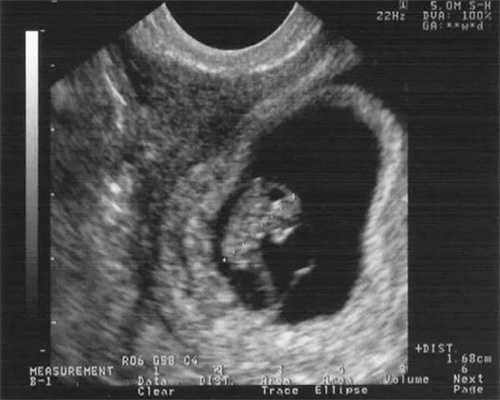

一般囊胚移植后的第二天,很多女性会出现腹胀的,这也是属于正常的现象。如果很严重就要立即就医。胚胎需要移植一周之后,才能通过抽血的方法查出怀孕,术后第2天的时候,血液里面还不会出现HCG,所以这个检查时间偏早,必须在一周之后,根据抽血的结果,进一步确定怀孕的情况。比如没有怀孕的情况下HCG的高度变化一般不会超过5ug/L,一旦结果超过10ug/L,即可确定怀孕。无需太过小心翼翼,保持原来的正常生活即可。